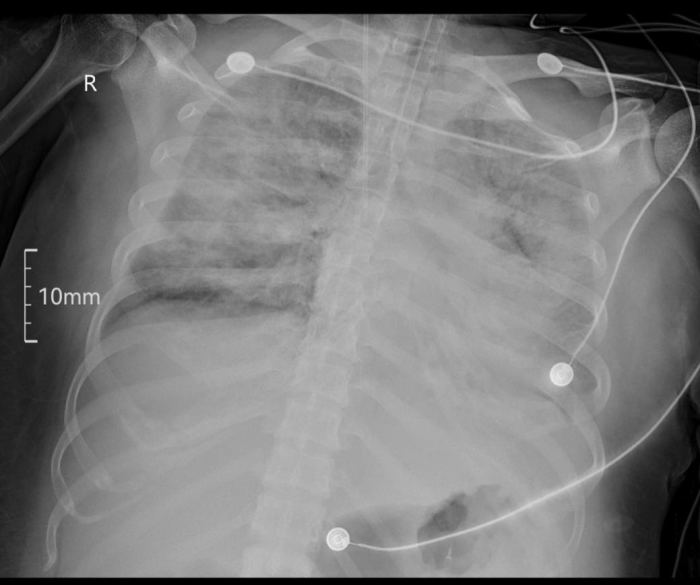

胸片显示,她的双肺几乎完全变白——这就是医生常说的“大白肺”,意味着肺里充满了液体,就像两块吸饱了水的海绵,无法正常换气。更要命的是,此前治疗使用的强效免疫抑制药物让她的免疫力极度低下,一种专挑免疫缺陷患者攻击的真菌——耶氏肺孢子菌也趁机而入,让她本就千疮百孔的肺部雪上加霜。

4月4日,“大白肺”区域明显透亮,肺纹理重新显现。